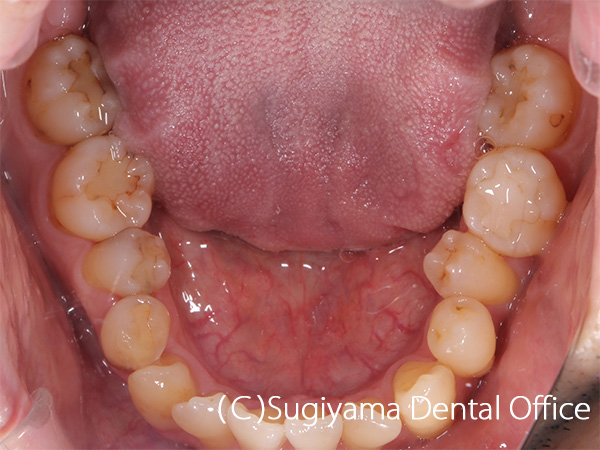

10歳の女性です。 術前写真を見ると、上の前歯2本が内側に傾斜していることがわかります(丸印)。 このような歯の傾斜によって下のあごの位置が奥に押し込まれ顎関節症になる方が少なくありません。

術後1年後には綺麗な歯並びになっただけでなく、機能的なあごの運動ができるようになりました。